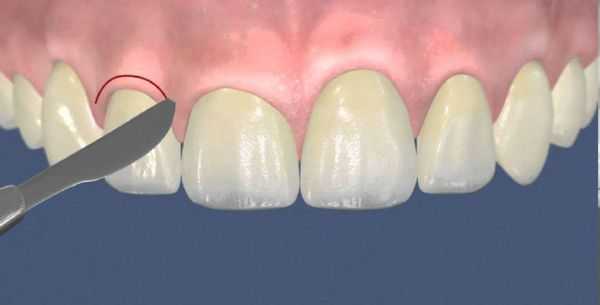

При гипертрофической форме гингивита перечисленные лечебные мероприятия могут не дать положительного результата. В таком случае для уплотнения разросшихся мягких тканей в межзубные сосочки делают инъекции склерозирующих средств. Если таким способом устранить разросшуюся грануляционную ткань не удалось, используют криодеструкцию (заморозку и удаление тканей с помощью жидкого азота), диатермокоагуляцию (иссечение слизистых тканей при помощи горячего инструмента) или удаление с помощью скальпеля — гингивэктомию [10] .

Выбор индивидуальной схемы лечения заболеваний пародонта зависит от этиологии и степени тяжести поражения. При пародонтите назначают профессиональную чистку, ревизию пародонтальных карманов, противовоспалительную и антибиотикотерапию. Из хирургических вмешательств в стоматологии проводят кюретаж, гингивотомию. Зубы 3-4 степени подвижности подлежат удалению. Действенными ортопедическими мероприятиями при заболеваниях пародонта являются шинирование и избирательное пришлифовывание.